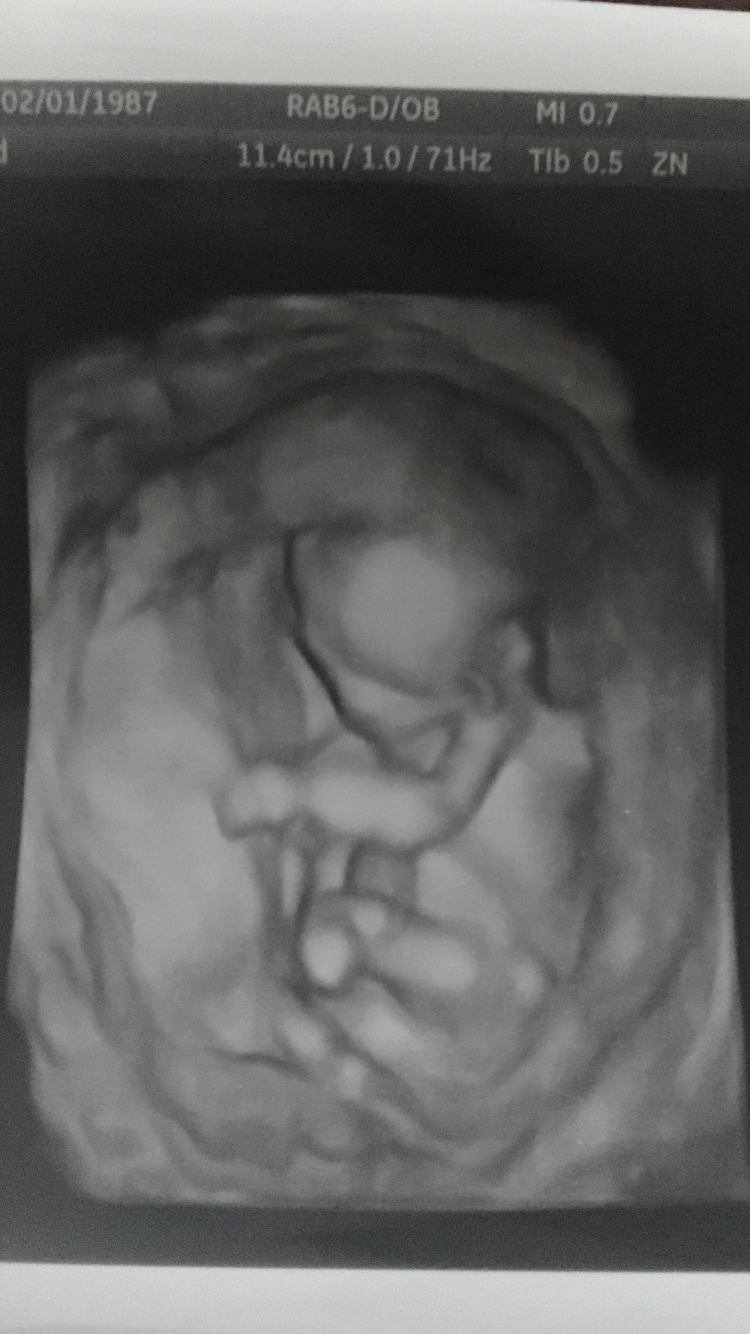

• Hey ladies . I had quite the scare early this morning . I woke up very early bleeding bright red blood very heavily and cramping . I called my nurse on call and she told me to go to the ER . Just finished a 45 min anatomy scan/ ultrasound and baby is somehow doing fine . My mind of course went to the worst place possible but they are reassuring me everything is ok . I have two SCHs which is what is causing the bleeding . It's so hard to stay calm . I was just feeling good and confident in this pregnancy since I just made it to second tri but this was quite the scare . Ah I hope it goes away !!

I wish I had been able to enjoy my early anatomy scan ( and that it hadn't been emergent ) more than I did but looking back my husband got some great pics now that I can enjoy since I'm calm . The one above is one of my faves . So cool to see

I thought SCH was more common during first tri . Does anyone know ? Or has anyone experienced SCH this late . This will be my second time . My first was at 5-6 weeks